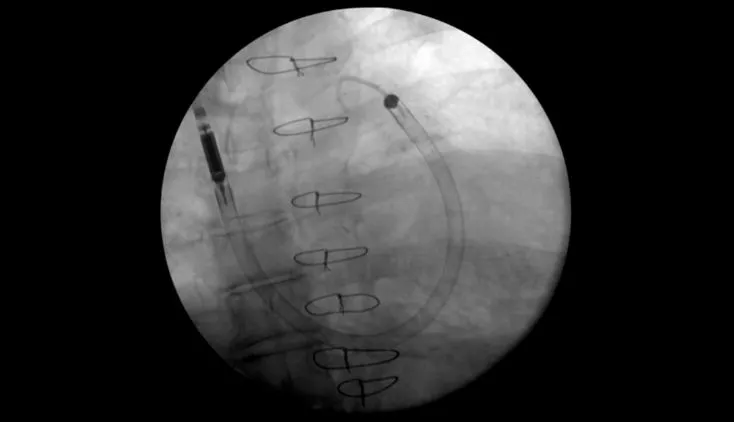

Impella RP Flex™ with SmartAssist® Insertion Animation

This animation depicts the primary steps for femoral insertion of the Impella RP Flex™ with SmartAssist®.